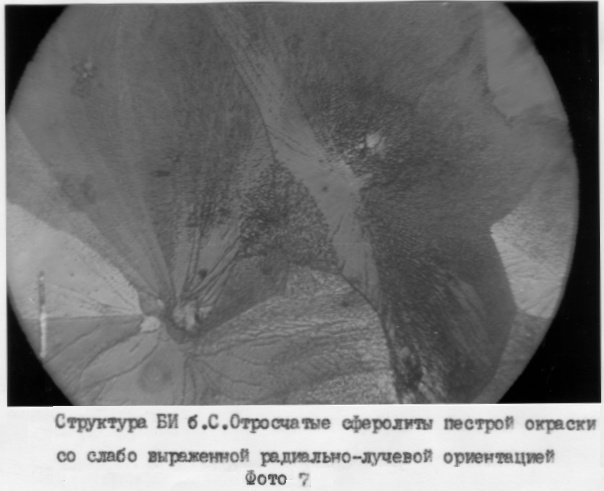

Пример 4, фиг.7. Б-ой С. Диагноз: ХП в фазе ремиссии. ИБ №94. На фиг.7 присутствует пестрой окраски отросчатый сферолит со слабо выраженной радиально-лучевой ориентацией.

Технология. На стеклянную пластину нанесли 0,1 мл БИ и поместили ее в зону Мэйо-Робсона б-ого. С., выдержали на протяжении 2 мин, высушили в термостате при Т=+18°С, изучили в поляризованном свете с КК, виден пестрой окраски отросчатый сферолит со слабо выраженной радиально-лучевой ориентацией. Одновременно произвели УЗИ ПЖ: головка 20 мм, тело 16 мм, хвост 25 мм, контуры неровные, эхогенность повышена, структура диффузно-неоднородная. Диагноз ХП подтвердился.